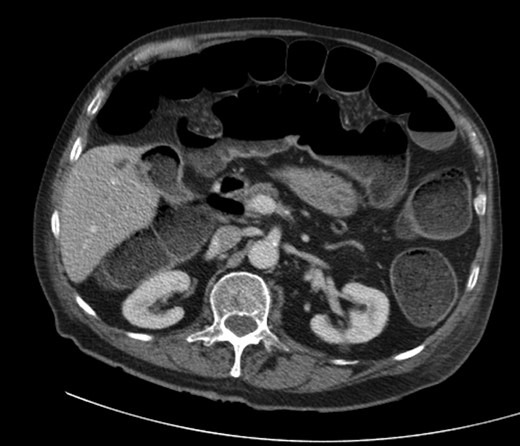

A 92-year male, with no significant co-morbidities apart from peptic ulcers, was admitted with 6 days of obstination. On examination he was dehydrated, with a hugely distended abdomen but no signs of peritonitis. Blood showed features of dehydration and plain abdominal X-ray demonstrated both small and large bowel dilatation, but no obvious causal pathology. A contrast-enhanced computed tomography scan revealed a 2.5-cm partially calcified gallstone impacted at the descending colon-sigmoid junction (Fig. 1). There was no stricture or diverticular disease distal to the stone. A cholecysto-colic fistula could be seen (Fig. 2), with a further smaller gallstone in the caecum (Fig. 3). The offending gallstone could be seen incidentally in the gallbladder on imaging 3 years previously (Fig. 4).

Cholecysto-colic fistula, with a thick-walled, dilated, gallbladder.